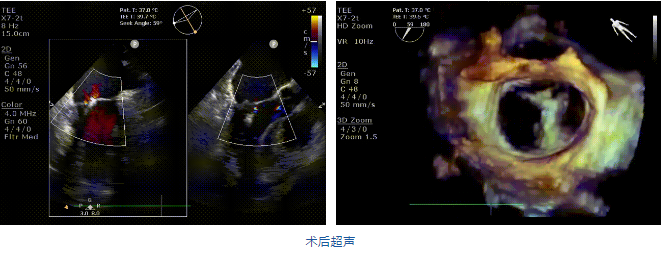

近日,海軍軍醫(yī)大學(xué)長海醫(yī)院心外科韓林教授團(tuán)隊(duì)在中國醫(yī)學(xué)科學(xué)院北京阜外醫(yī)院/云南省阜外心血管病醫(yī)院潘湘斌教授團(tuán)隊(duì)的支持下成功應(yīng)用我國創(chuàng)新器械JensClip為一例二尖瓣重度反流患者開展二尖瓣緣對(duì)緣修復(fù)手術(shù)。在韓林教授團(tuán)隊(duì)的密切配合下,手術(shù)圓滿完成,患者重獲“心”生。術(shù)后即刻超聲顯示二尖瓣反流顯著改善,術(shù)畢即刻拔管,患者恢復(fù)良好。

在阜外醫(yī)院潘湘斌教授團(tuán)隊(duì)的支持下,手術(shù)經(jīng)股靜脈-房間隔入路,采用全身麻醉插管,在TEE和DSA引導(dǎo)下完成房間隔穿刺。置入JensClip瓣膜夾系統(tǒng)后,在左房調(diào)整瓣膜夾的位置和軸向,后進(jìn)入左室,在TEE引導(dǎo)下捕捉二尖瓣前后瓣葉,并關(guān)閉瓣膜夾。經(jīng)TEE反復(fù)確認(rèn)手術(shù)效果后最終鎖定并釋放瓣膜夾。術(shù)后即刻超聲顯示瓣膜夾位置穩(wěn)定,功能良好,二尖瓣反流由術(shù)前4+減少至微量,手術(shù)圓滿成功。